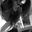

Hippocampal subfield segmentation was performed using a module in FreeSurfer software that was designed for the purpose; the module employs a tetrahedral mesh-based probabilistic atlas built from manually delineated hippocampus in both in vivo and ex vivo data (Iglesias et al., 2015). Using this algorithm, the overall volumes of the bilateral hippocampus and their subfields were obtained. Two sets of segmentations with different levels of hierarchy were generated: (1) head, body, and tail (usually referred to as subregions); and (2) CA1, CA3 (which contains CA2), CA4, the molecular and granule cell layers of the dentate gyrus (GC-ML-DG), the molecular layer, subiculum, presubiculum, parasubiculum, fimbria, and hippocampus–amygdala transition area (HATA). An example of the segmentation for a healthy subject is shown in Figure 1. All segmentation was visually verified following a quality control protocol that is similar to the ENIGMA protocol2. In brief, the segmentation of each subject was independently visually checked by two coauthors (LZ and MT), and any subject with segmentation results judged to be incorrect was excluded; no such segmentation failures occurred.

Figure 1. An example of hippocampal subfield segmentation in healthy Han Chinese individuals living on the plain. Upper row: (A) sagittal, (B) coronal and, (C) axial view of the hippocampus in the brain; Lower row: 3D reconstruction of the hippocampal subfields in (D) dorsal, (E) lateral, (F) frontal and, (G) medial view.